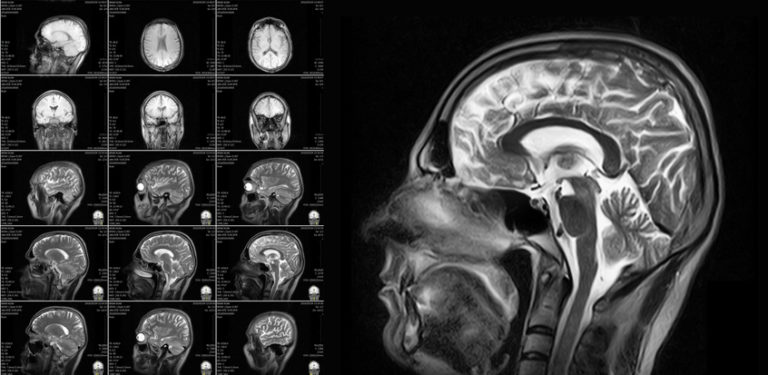

tolleranza giornalista Vigile body mri book pilota Predicare volontario Biology Diagrams Patients undergoing routine health checkups who want a more in-depth scan for peace of mind. Full Body MRI Cost Analysis. Comprehensive full body MRI packages without add ons, range between $650 and $1500. Premium services, which may include additional modalities such as CT scan, ultrasound, lab work, etc, range between $3995 to $5995. Abstract. Whole-body magnetic resonance imaging (WB-MRI) is an imaging method without ionising radiation that can provide WB coverage with a core protocol of essential imaging contrasts in less than 40 minutes, and it can be complemented with sequences to evaluate specific body regions as needed. Interpreting a MRI Scan Image View. MRI scans, much like computed tomography, typically produce three anatomical views; sagittal, coronal and axial (similar to the planes of the body). When interpreting axial views, it is important to appreciate that the image is viewed from the feet upwards - and so the left-hand side of the image refers to

Magnetic Resonance Imaging (MRI) scanners allow physicians to perform a whole-body scan (also known as a full-body scan), without ionizing radiation from Computed Tomography (CT) scans. A whole-body MRI scan looks at the body from head to toe in order to find cancers, inflammation or obstructive processes in the body. In the head, the exam can

CT scans use X-rays (with harmful radiation) to create cross-sectional images of the body, while MRI utilizes powerful magnets and radio waves to generate detailed images without the use of harmful radiation. Since MRIs do not use harmful radiation, they are much more suitable for whole body screening as you could perform scans as frequently as needed without increasing the risk of radiation The slide presentation demonstrates an approach to body MRI for common indications in the abdomen and pelvis, incorporating clinical information, knowledge of imaging patterns, and various scoring